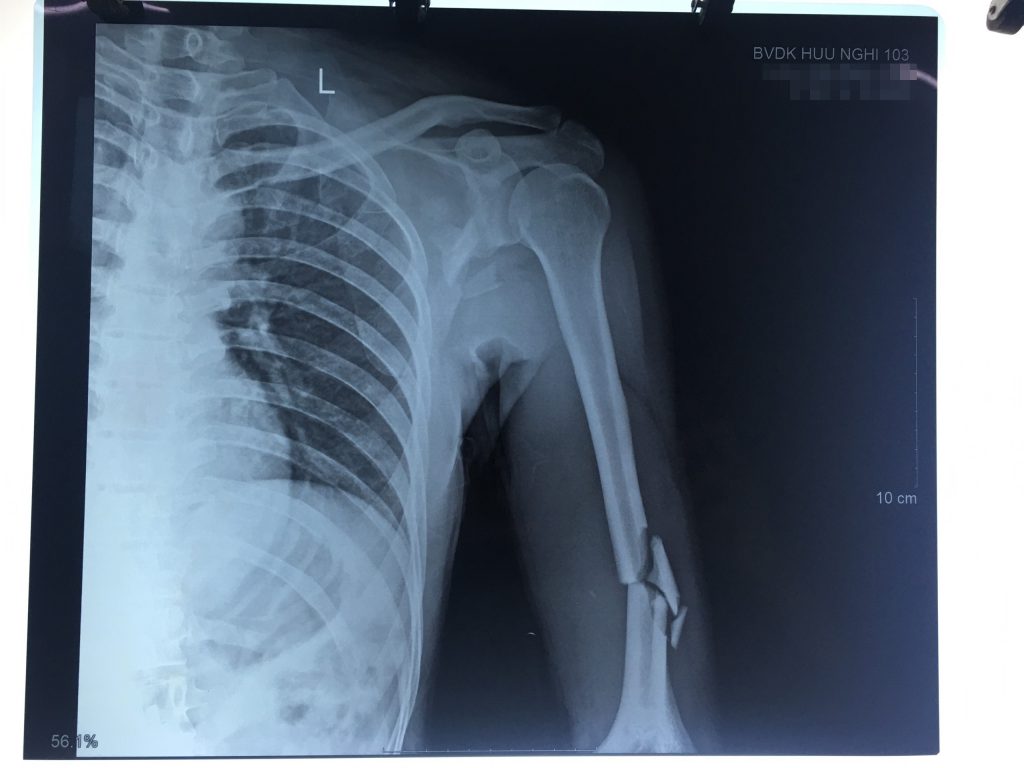

Sau khi đánh giá toàn trạng của bệnh nhân, xử trí ban đầu, bệnh nhân được chỉ định chụp X Quang và chẩn đoán: Gãy kín 1/3 dưới xương cánh tay + gãy kín 1/3 giữa hai xương cẳng tay + gãy xương bả vai trái do TNLĐ.

Bệnh nhân được chỉ định nhập viện để phẫu thuật kết hợp xương tay và xương cẳng tay bằng nẹp khóa.